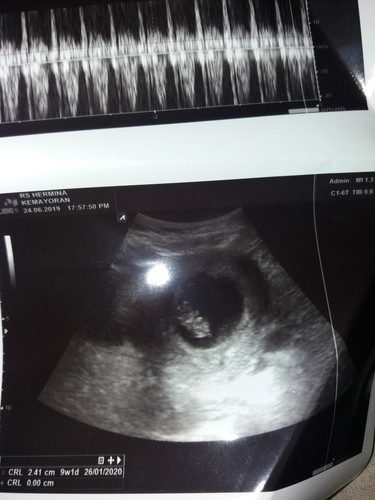

usg pertama

Alhmdllh bunda penantian 5thn akhirnya doa saya djwb oleh Allah.. UK saya skrg 10week seharusnya kalau dhitung dr hpht..tapi kemarin saya usg janinnya ukuran 9w ..faktor apa y bunda apa karena saya ga minum susu hamil jd bbj nya kurang...??makann apa yg bgus bwt nmbah bbj bunda"? Terima kasih sebelumnya